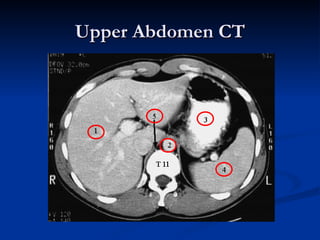

Upper Abdomen CT